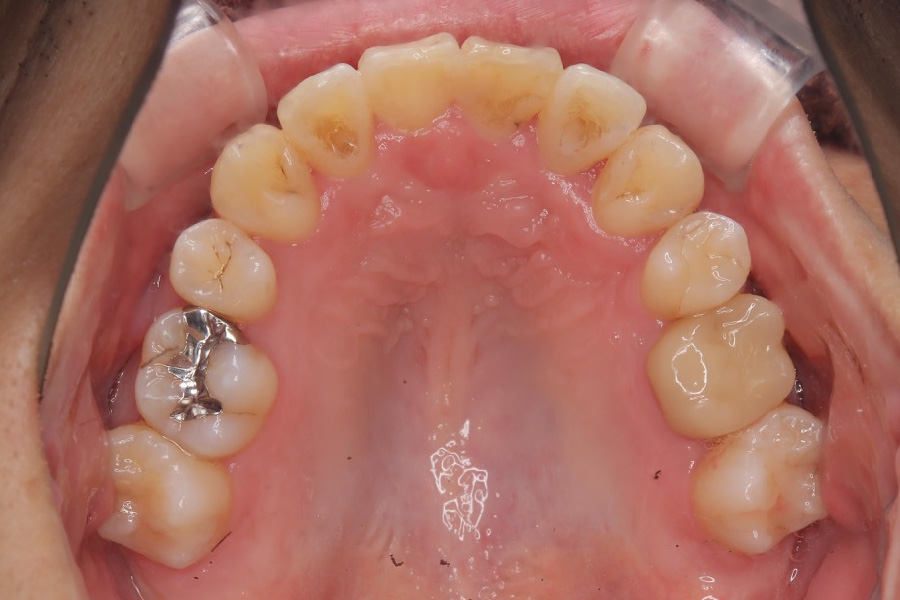

治療前

主訴 歯全体のガタつきが気になる

治療内容 インビザライン矯正

小臼歯抜歯